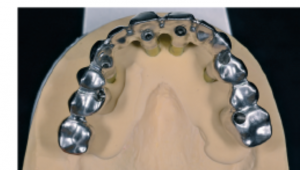

d. Estructura protésica definitiva fresada mediante CAD/CAM con orientación precisa de los canales de tornillo angulados.